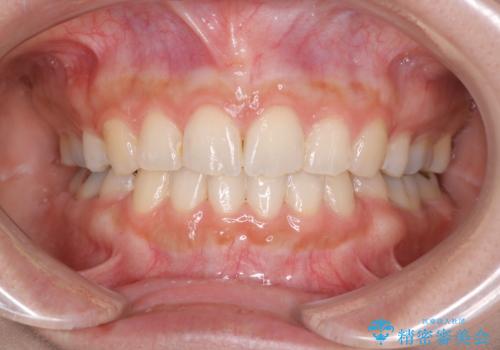

口元をさげたい ワイヤーによる抜歯矯正

- 口元が出てるのが気になるとのことで来院されました。

上下左右前から4番目の歯を抜歯して前歯を後方に下げて、口元を下げる計画としました。